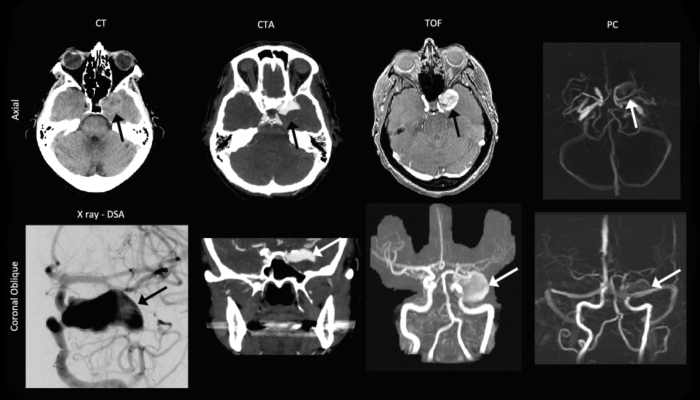

Fig. 1.

Pre-operative computed tomography (CT), CT angiography (CTA), digital subtraction angiography (DSA), noncontrast-enhanced time-of-flight (TOF) imaging, and phase-contrast (PC) imaging. The aneurysm (black and white arrows) was clearly depicted on the combination of axial and coronal orientations. The coronal TOF and the PC images are maximum-intensity projections.

The PC images highlighted only the region of flowing blood. The high-resolution PC MRI-derived velocity measurements confirmed that the velocities toward the periphery of the aneurysm were on the order of 5cm/s, whereas samples in the center of the fundus were around 1.5cm/s (Fig. 2). Figure 2 also shows the force vectors generated by the blood. These vectors are analogous to the pressure, though they show the direction of the fluid force. A higher pressure was observed in the aneurysm where the flow jet reversed or where the velocity was small.